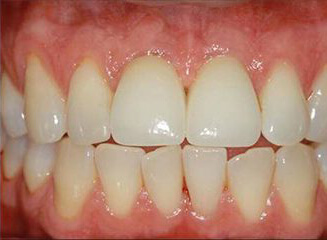

Проблема. Широкие промежутки между зубами и сколы на режущих кромках зубов.

Решение. Эстетическое пломбирование 4 зубов.